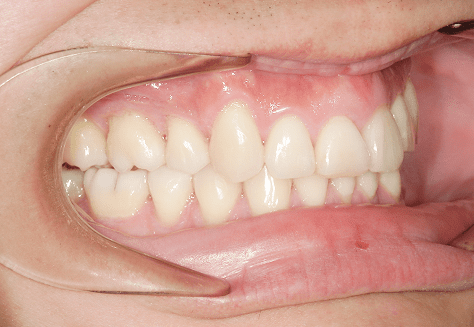

M.U

治療前

治療後

主訴

下の歯が特にガタガタなのが気になる。上の前歯が1本反対になっている。

診断

下顎前突・叢生・反対咬合

年齢/性別

20代/男性

抜歯部位

非抜歯

使用装置

上下インビザライン(PBM使用)

保定装置

ビベラリテーナー

料金

初回資料採得・・・・・・・30,000円

診断料・・・・・・・・・・33,000円

動的治療終了時資料採得・・5,500円 -

基本料金

950,000円

診察料金

5,500円×16回

治療期間

1年7カ月